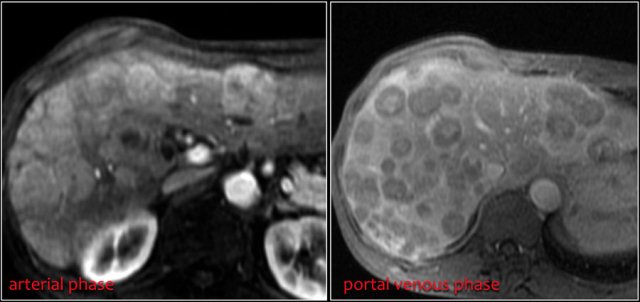

Liver metastases are usually hypervascular and can show central necrosis.

Same patient.

Four years after the initial CT multiple liver metastases are seen.

Notice hypervascular enhancement pattern in the late arterial phase.